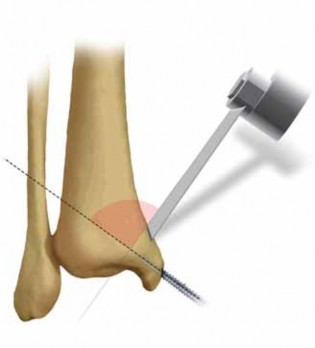

I prefer to continue the medial incision longitudinally, directly in line with the axis of the medial malleolus, extending just proximal to the supramalleolar region ( FIG 5A).

8.

After exposing the malleolus, without violating the perios-teum, the distal tip of the anterior and posterior colliculus of the medial malleolus must be predrilled ( FIG 5B) and tapped retrograde for two parallel, 3.5-mm interfragmentary cortical or 4.0-mm partially threaded cancellous screws.

9.

An oblique osteotomy directed toward the shoulder of the medial ankle mortise is performed using a very thin oscillating saw blade.

1.

This osteotomy is incomplete, advancing only to the level of the medial subchondral bone.

2.

The osteotomy is completed by gentle levering of a thin wide osteotome on the inner cortex ( FIG 5C).

10.

At this time, an anterior and partial posterior capsulotomy of the medial malleolus is needed to allow inferior mobilization of the malleolus. The deltoid vessels perfusing the medial body of the talus are protected with gentle retraction.

11.

Patients requiring this transmalleolar approach will routinely benefit from the associated anterolateral incision for optimal visualization of the proximal neck and body of the talus during reconstruction.